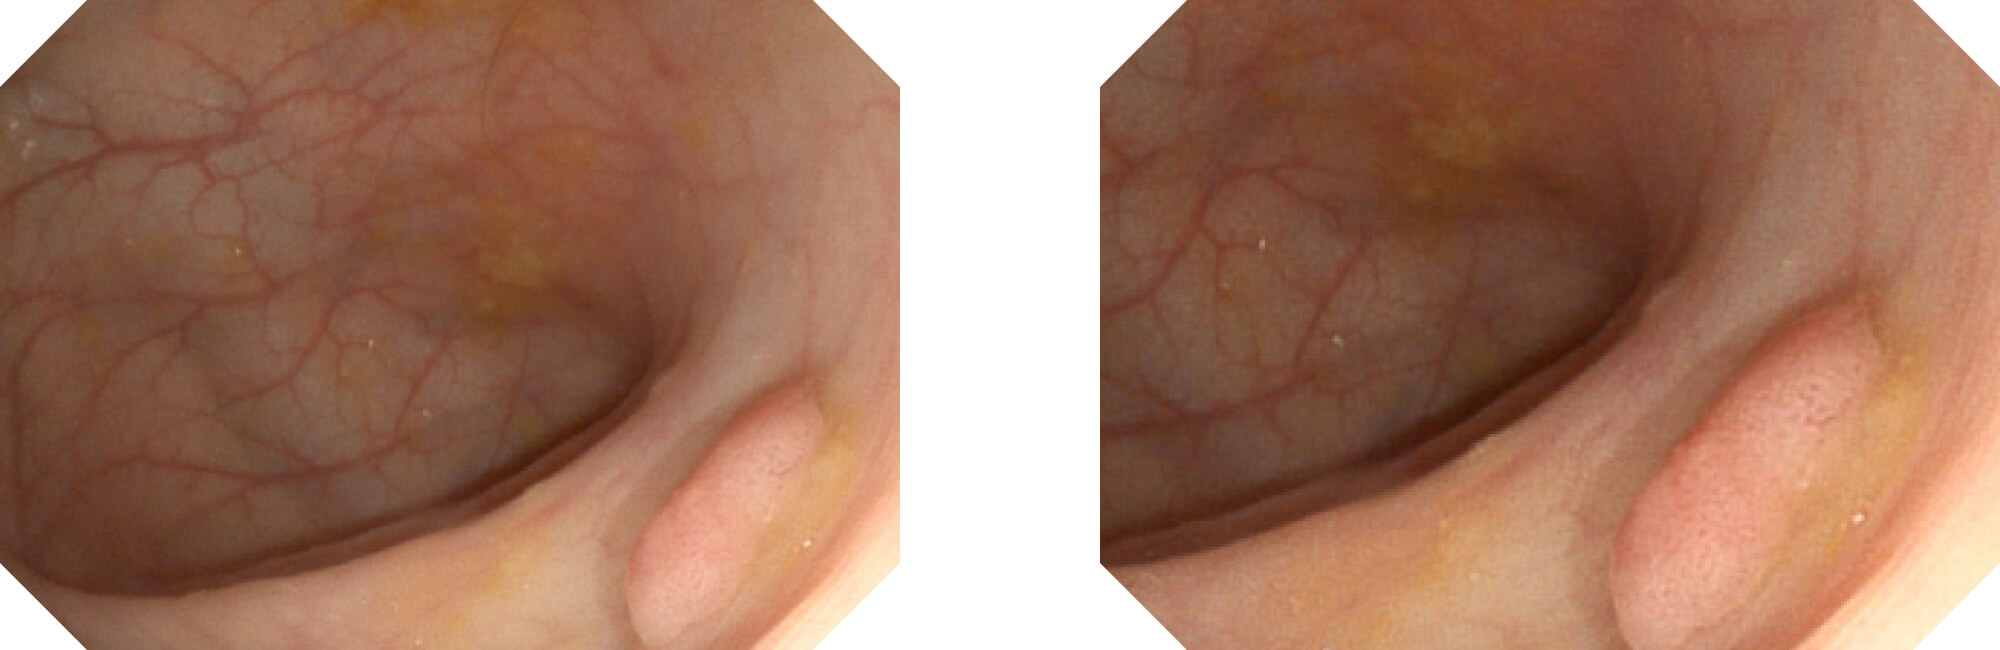

高清数字信号结合构造强调和色彩增强,多重图像处理技术能让每一个图像都清晰可见。

构造强调

色彩增强